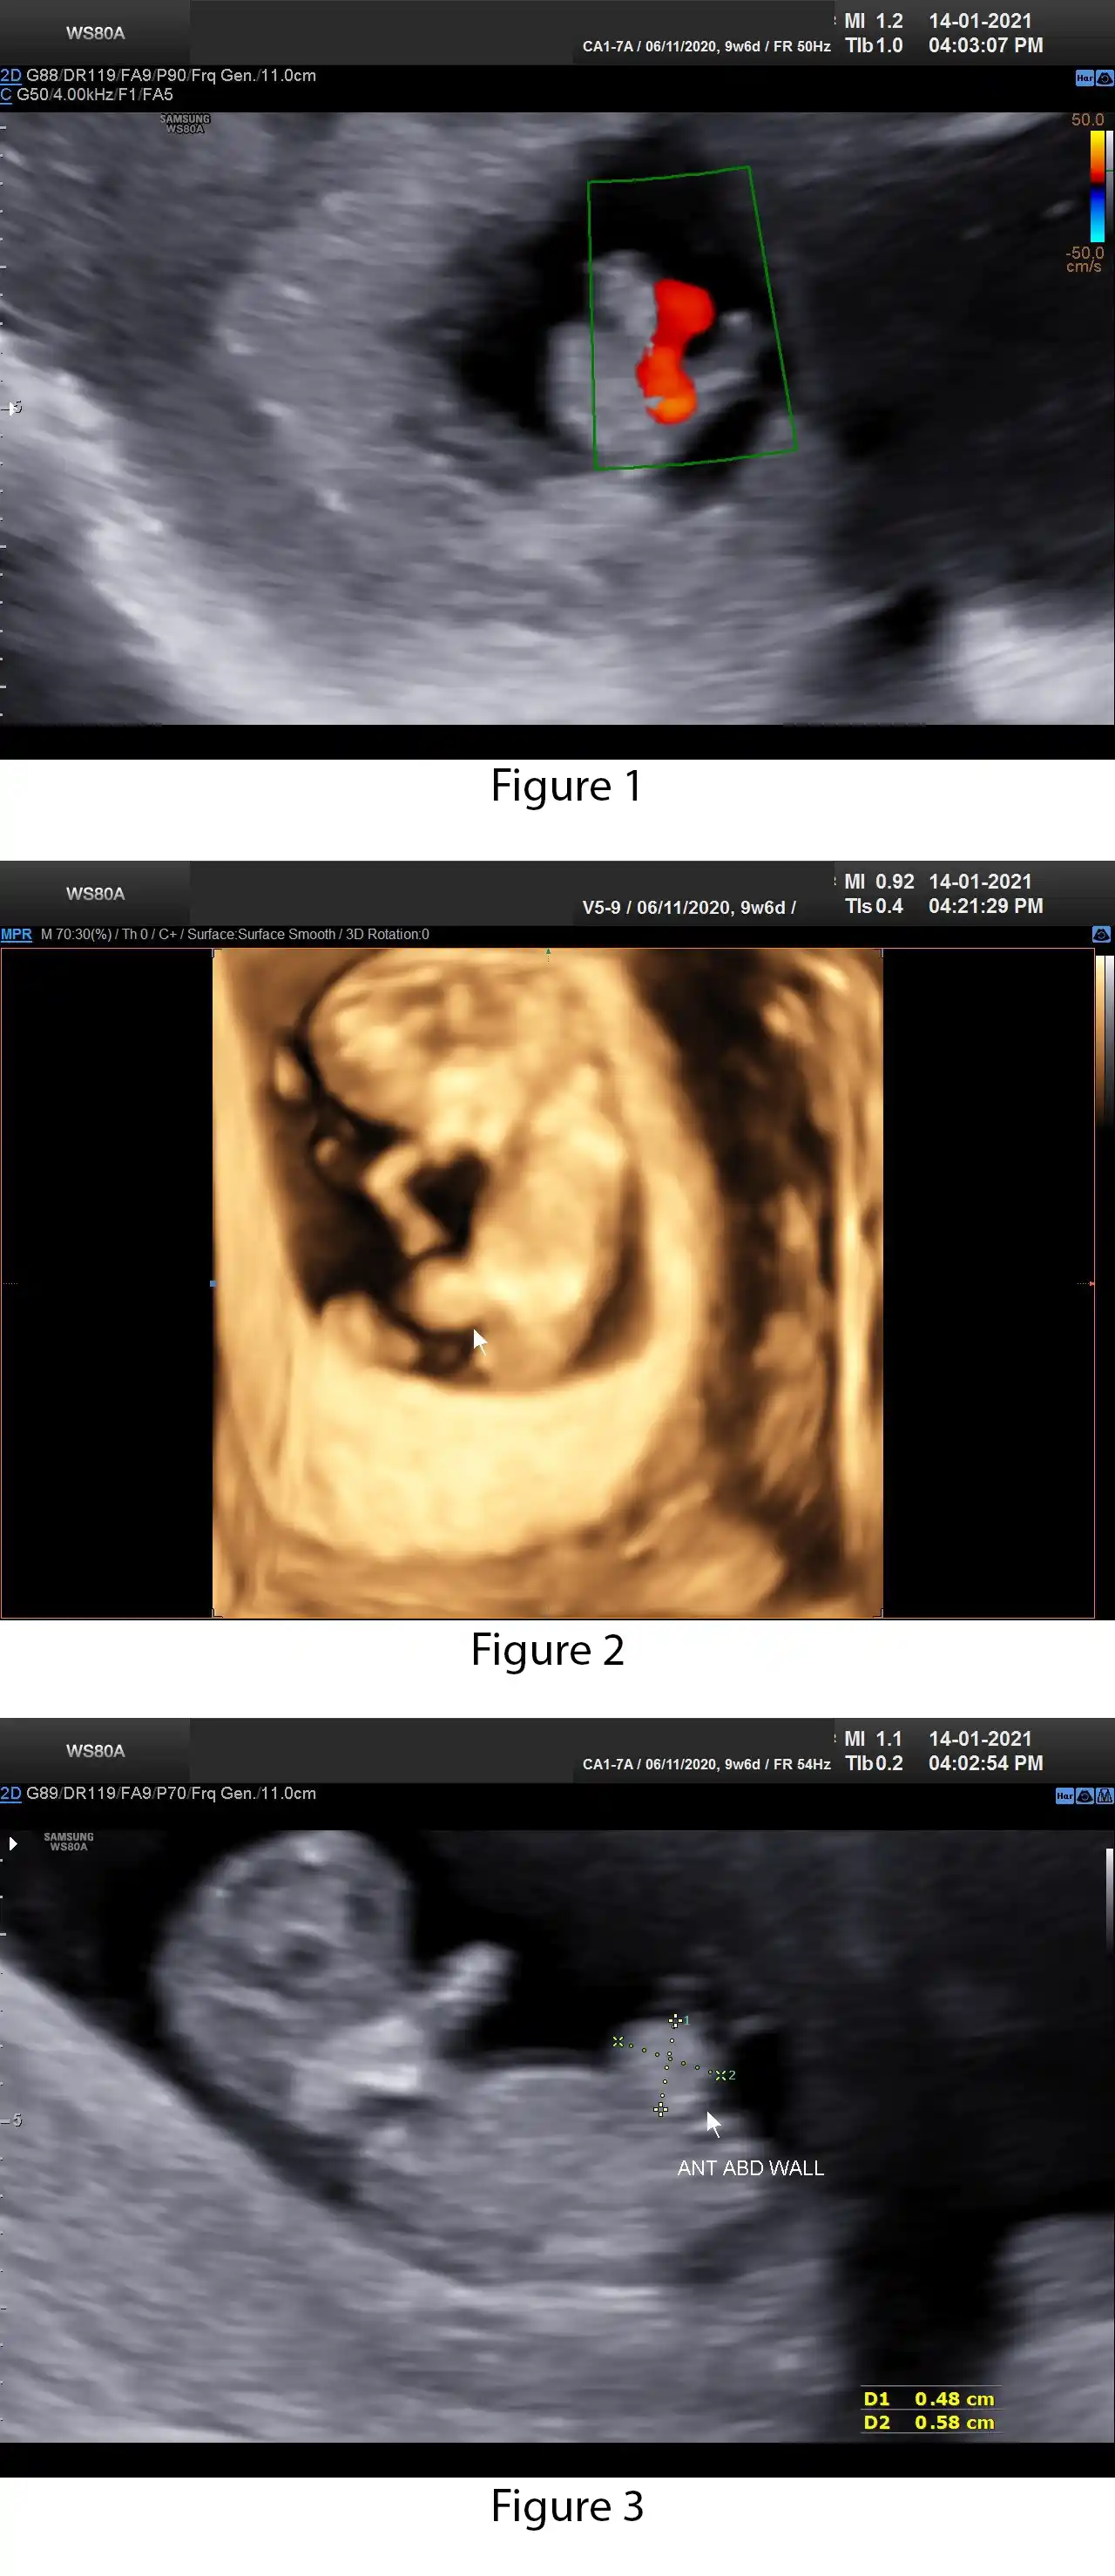

Features of Physiological Gut Herniation.

Presence of fetal bowel outside the anterior abdominal wall, at the base of the umbilical cord.

It should not be seen after 12-13 weeks gestational age.

It should never contain herniation of other organs, such as the liver.

The extent of herniation is comparatively small (often <7 mm).